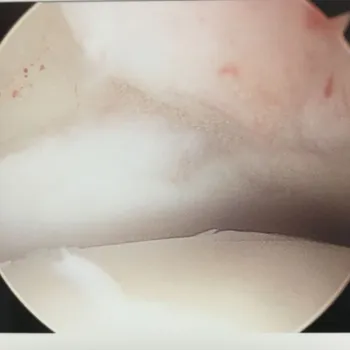

3.  ARTHROSCOPIC CLASSIFICATION:

A. Pritsch Et Al:

Stage I   Intact overlying cartilage.

Stage II   Soft overlying cartilage.

Stage III  Frayed overlying cartilage.

B. Cheng and Ferkel:

Stage A  Smooth, intact, but soft or ballotable.

Stage B  Rough surface.

Stage C:  Refibrillation and/or fissuring.

Stage D:  Flap present or bone exposed.

Stage E:  Loose, undisplaced fragment.

Stage F:  Displaced fragment.